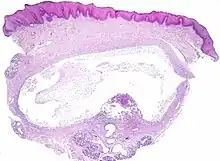

The histologic appearance is similar to mucoceles from other locations. The spilled mucin causes a granulation tissue to form, which usually contains foamy histiocytes.[1] Ultrasound and magnetic resonance imaging may be useful to image the lesion.[4] A small squamous cell carcinoma obstructing the Wharton duct may require clinical examination to be distinguished from a ranula.[5]